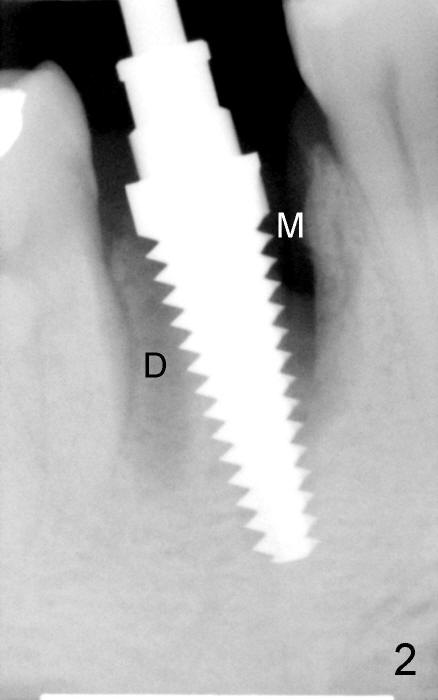

The patient returns for extraction and immediate implant after 7 days of oral Amoxicillin. There is a deep pocket mesiolingually in addition to the mesiobuccal fistula (Fig.1 <). The metal crown and then the tooth are sectioned. The crack of the mesial root is confirmed during extraction. The coronal portion of the mesiobuccal plate is defective, corresponding to the fistula. Both the mesial and distal sockets are large with a thin septum in between. Osteotomy is established at the base of the septum, slightly toward the mesial socket, as evidenced by a 5x20 mm tap in place (Fig.2). Finally, a 7x17 mm implant is placed (Fig.3 I; A: abutment; G: bone graft). The insertion torque is more than 60 Ncm.

In this case, the root fracture is associated with dense bone (type II). Primary stability is easily achieved. In addition, apical to the original sockets, the implant has five of bony walls, whereas the rest portion two (buccal and lingual). Therefore, do not miss the opportunity of immediate implant.